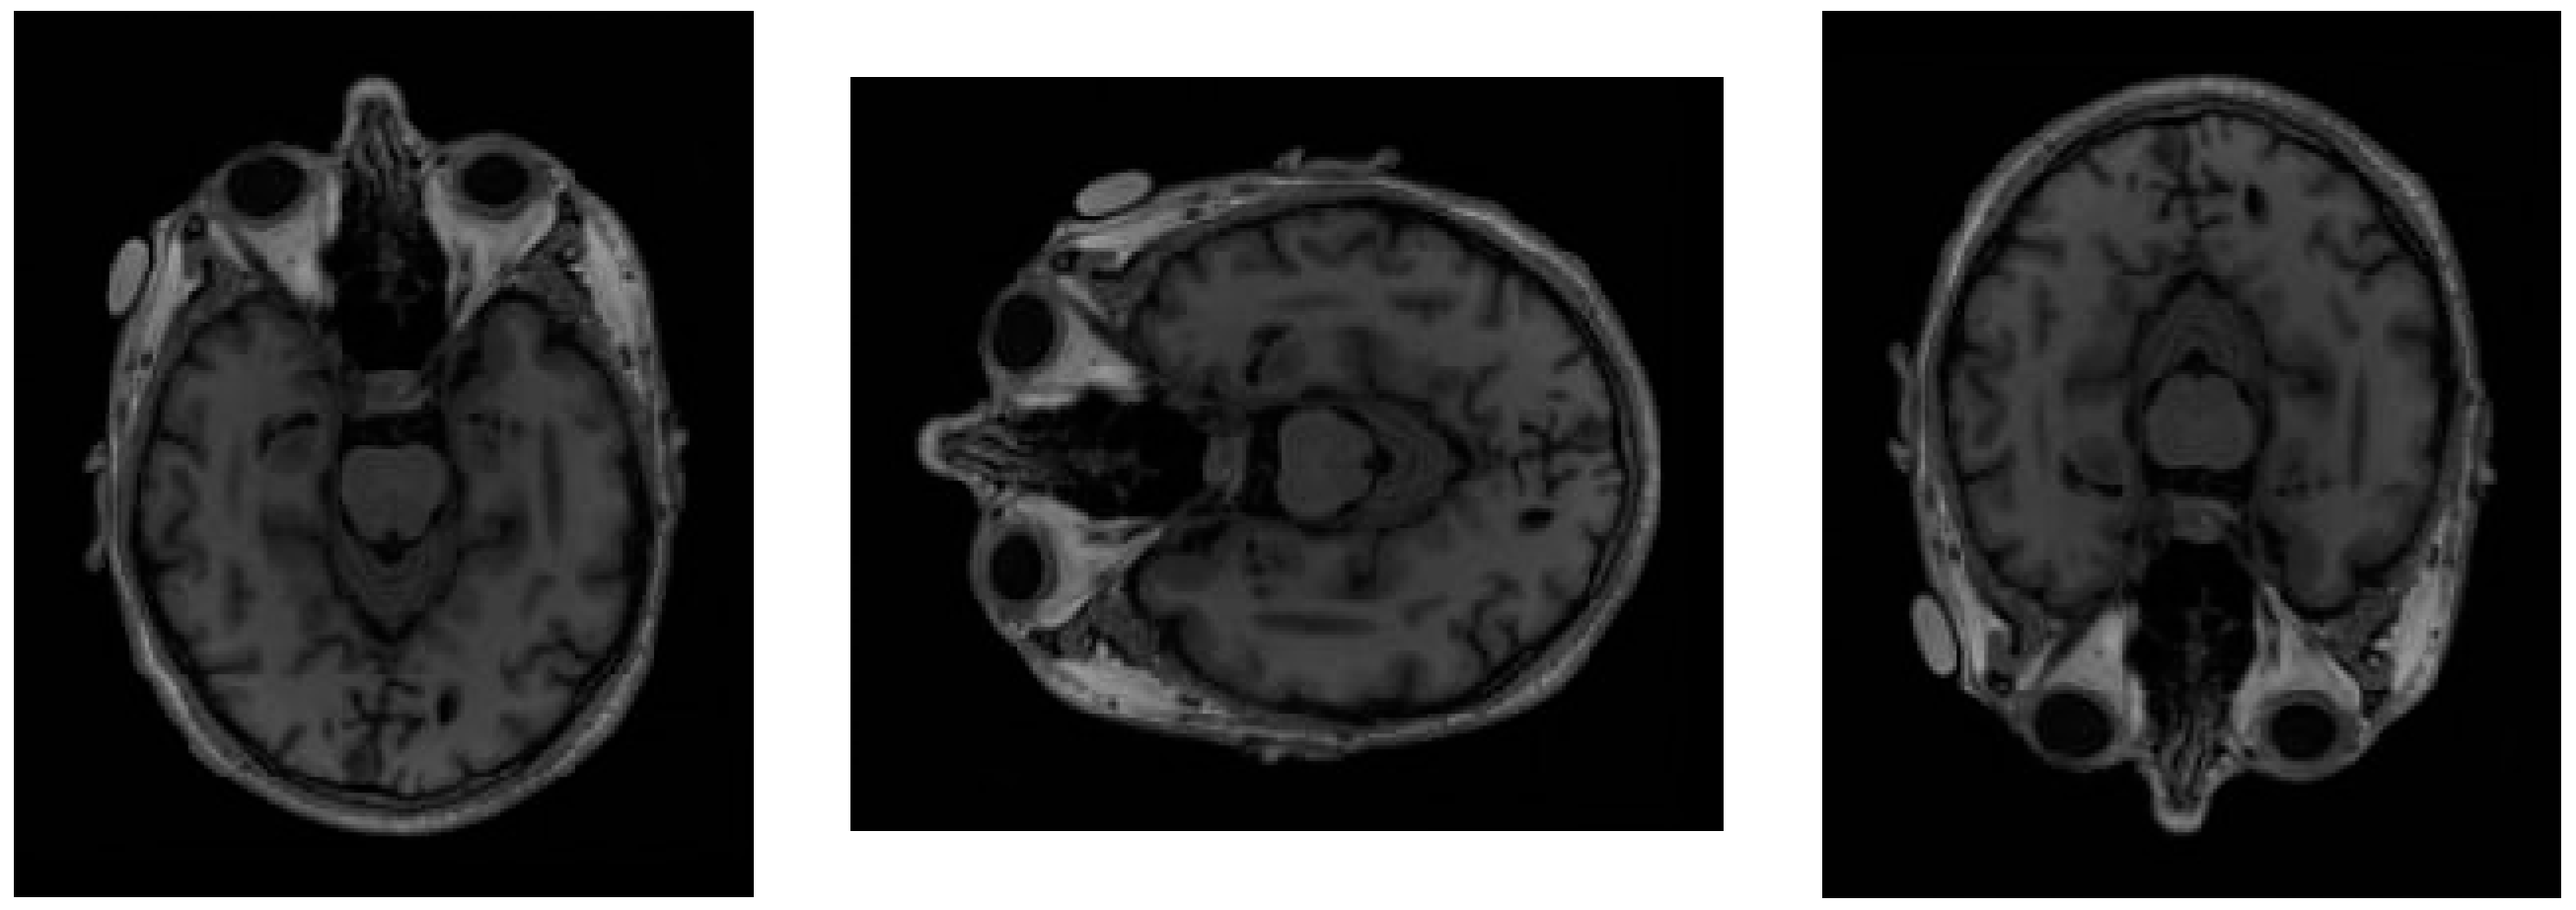

To enhance the model’s ability to recognize image features and to mitigate overfitting, several regularization strategies were employed during model training. Data augmentation techniques, including random horizontal and vertical flips and image enhancement, were applied to increase dataset diversity. Additionally, early stopping based on validation loss and careful learning rate scheduling were used to prevent overfitting. This approach increases the diversity of the training data without altering the inherent details and features of the images. Horizontal flipping simulates the left-right differences that may occur in anatomical structures among different individuals, while vertical flipping helps the model learn the impact of vertical position changes on pathological tissue features. In addition, image enhancement techniques were applied, including Contrast Limited Adaptive Histogram Equalization (CLAHE) to improve local contrast and Gaussian filtering to suppress noise while preserving structural boundaries. Figure 4 presents a sample image from the dataset alongside two types of random variations, one using horizontal flipping and the other using vertical flipping.

Figure 4. A sample image from the test dataset (left) alongside two augmentation result images: horizontal flipping (middle) and vertical flipping (right).